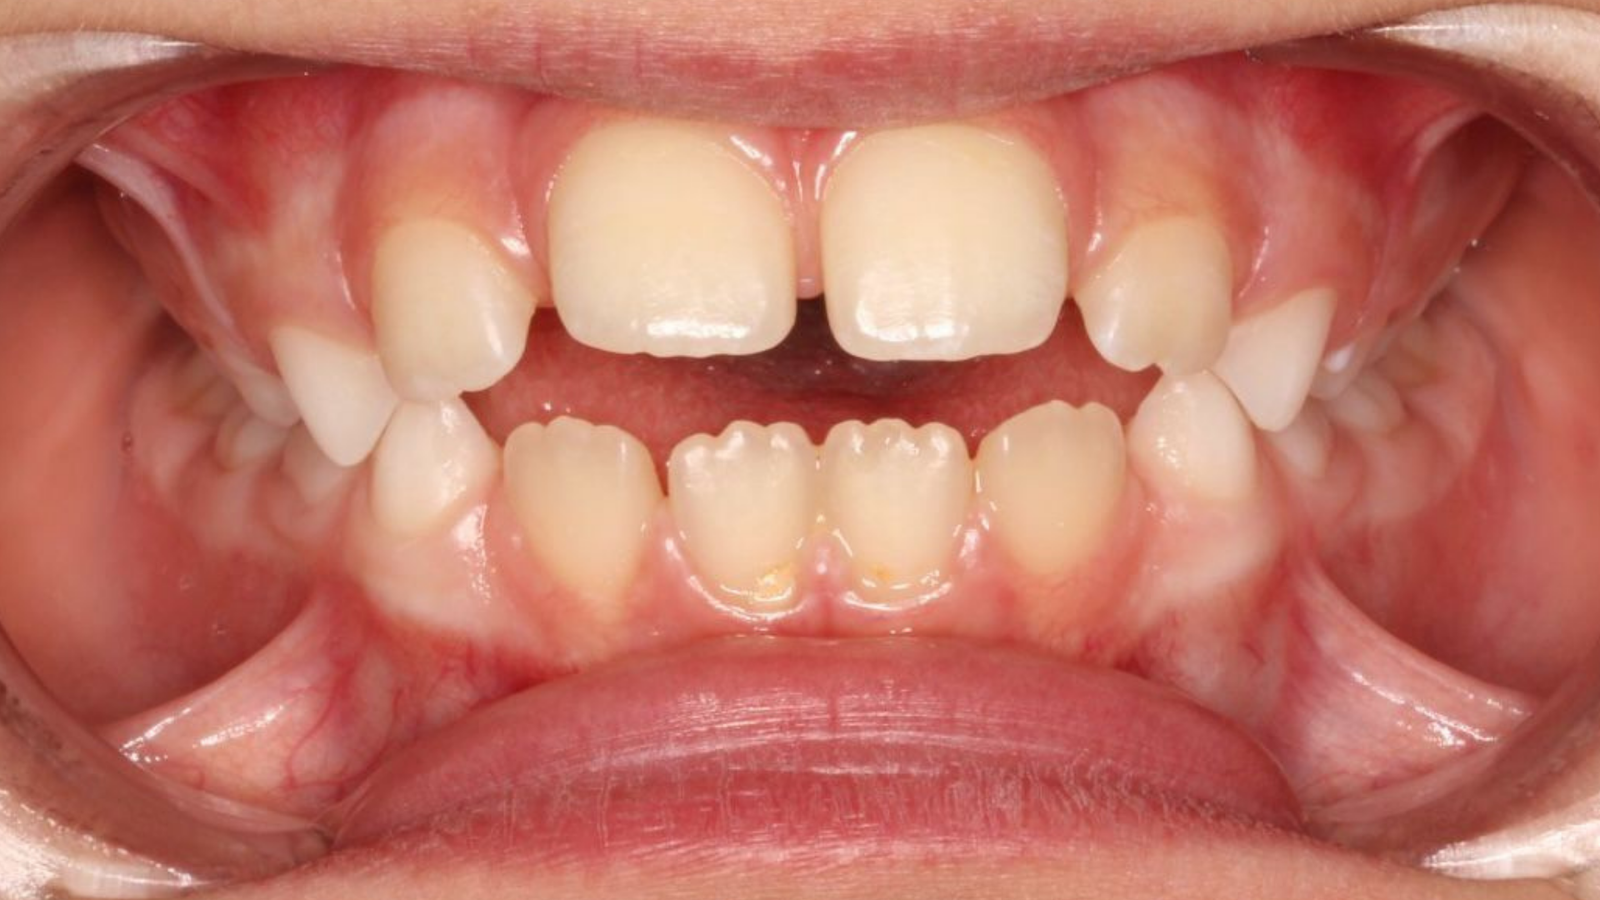

La Supervisión del Crecimiento de nuestros hijos es fundamental para garantizar un desarrollo bucal adecuado.

Con una atención cuidadosa en las fases clave del desarrollo, podemos asegurar una Salud bucal óptima y Resultados duraderos para nuestros hijos.

Sano Desarrollo correcto prevención desde pequeño!